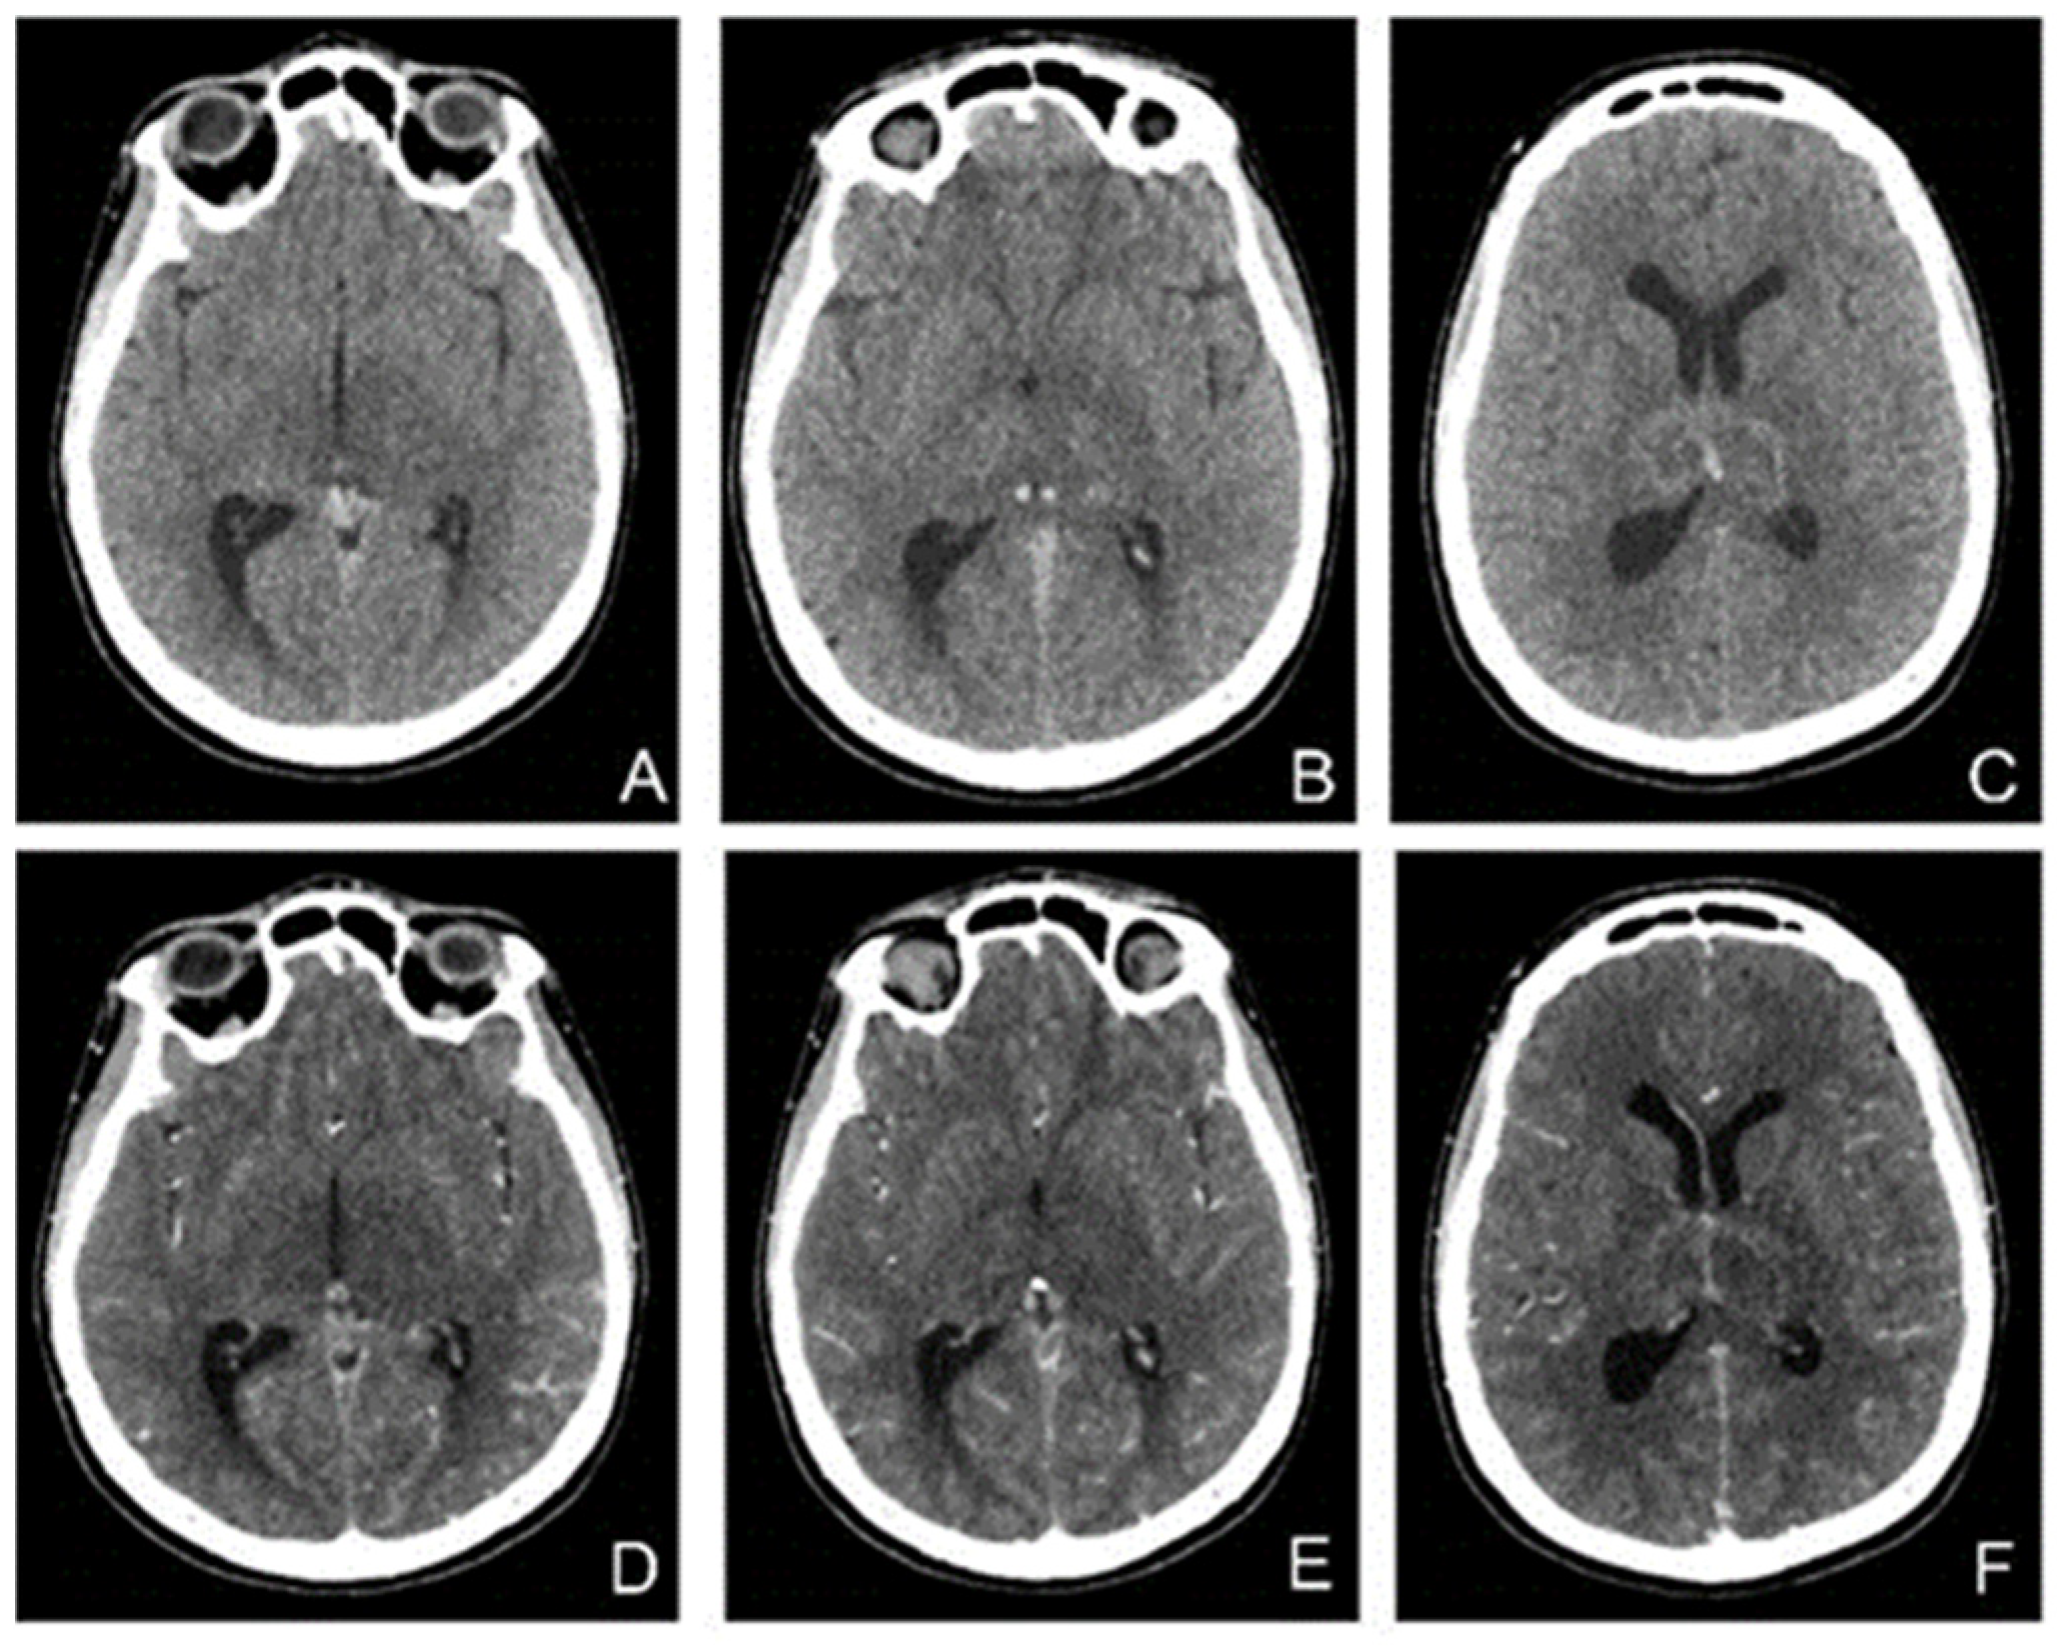

In the following days, the patient′s condition continued to worsen. She did not respond to nociceptive stimuli, spontaneously mobilized her limbs, and had involuntary movements of the jaw. Considering the unfavorable and unpredictable evolution, in agreement with the family, we decided to perform therapeutic abortion. A new brain CT was performed (Figure 7).

Figure 7.

CT without contrast (A–C) and with (D–F) contrast enhancement shows hyperdensities in the Galen vein and internal cerebral veins with nonhomogeneous thalamic nuclei. After contrast enhancement, there was a slight enhancement in the veins and hypoperfusion of the thalamic nuclei.